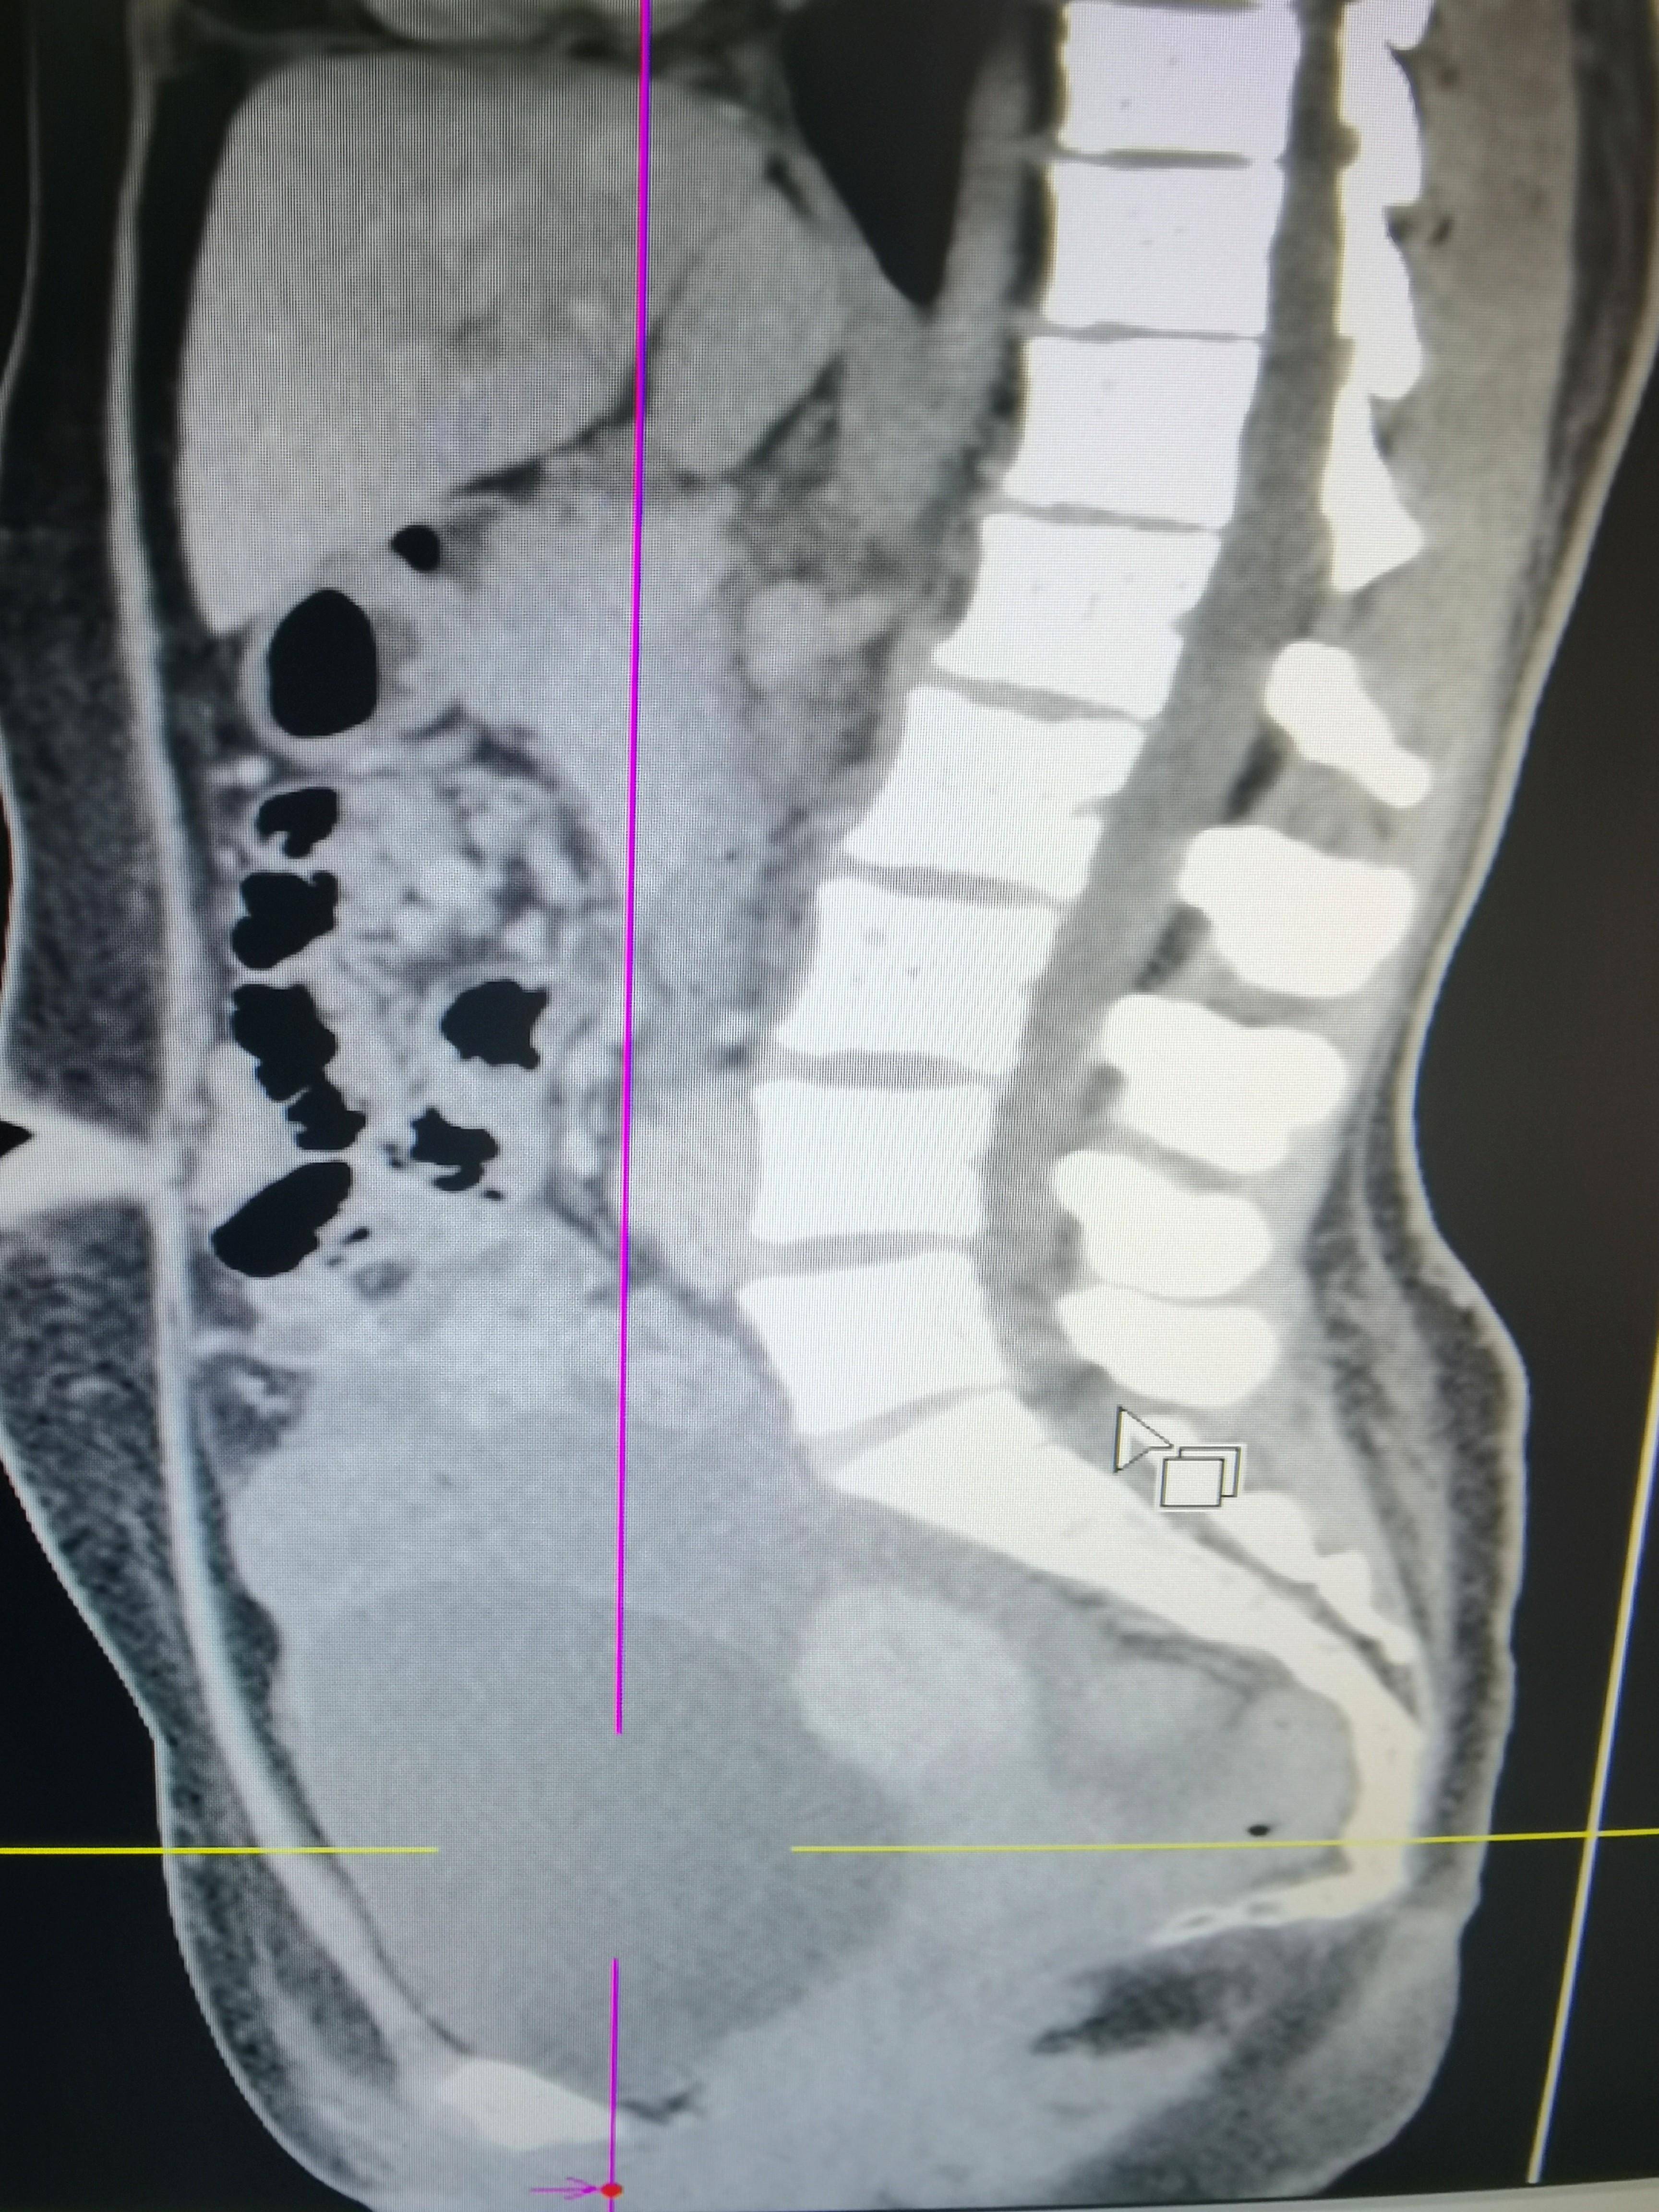

◈ 2021年7月8日,患者为求手术治疗就诊于我院门诊,行腹部CT检查提示:盆腔见不规则低密度影,包绕膀胱及子宫,与双侧附件及邻近肠管、右侧髂血管分界不清,三期CT值约为28Hu、27Hu、34Hu,其内密度不均,可见片状高密度影及钙化密度影。检查诊断:盆腔占位病变,考虑粘液瘤可能性大,建议进一步检查(因放射科无法获得胃肠间质瘤诊断及治疗病史)。结合患者病史及腹部CT结果,目前患者肿瘤包绕膀胱及子宫,与双侧附件分界不清。术中可能需要切除附件,因患者为年轻未婚未育女性,且直接手术的临床价值尚不明确,暂不考虑手术治疗。建议继续给予口服伊马替尼400mg QD。

2021年7月8日 腹部CT